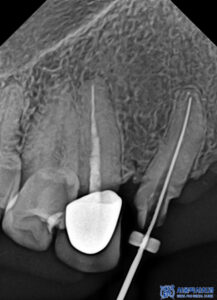

이후 신경치료를 진행하여

치아 내부의 감염된 신경과 염증을 제거하고,

재감염을 예방할 수 있도록

근관을 꼼꼼하게 소독·충전하였습니다.